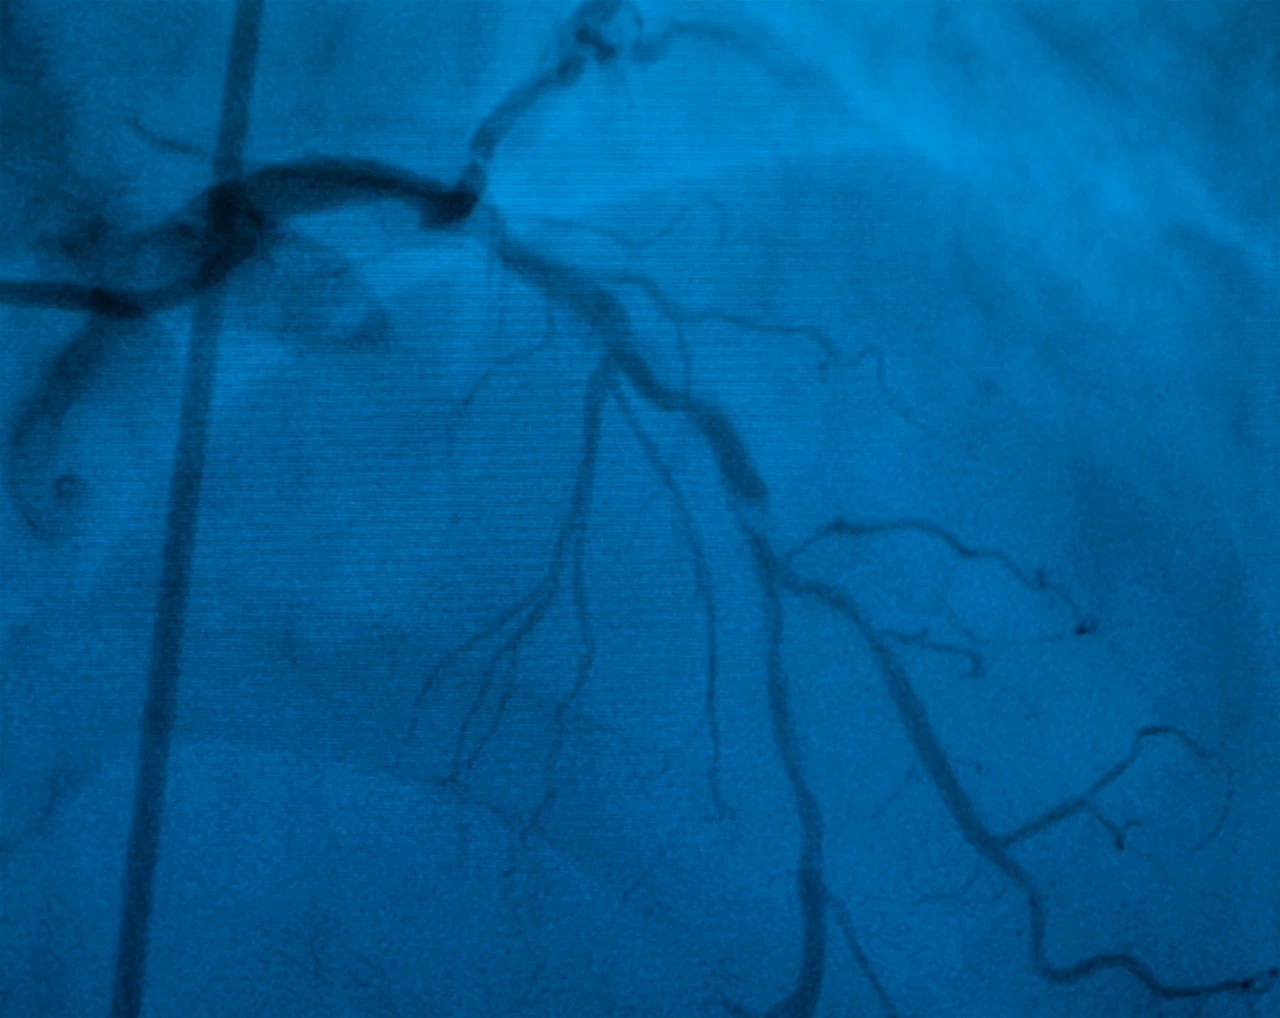

Más allá de la intervención terapéutica, las salas de hemodinamia también juegan un papel crucial en el diagnóstico y seguimiento de diversas patologías cardiovasculares, mediante técnicas especializadas como la angiografía.

Angiografía coronaria realizada en una sala de hemodinamia.